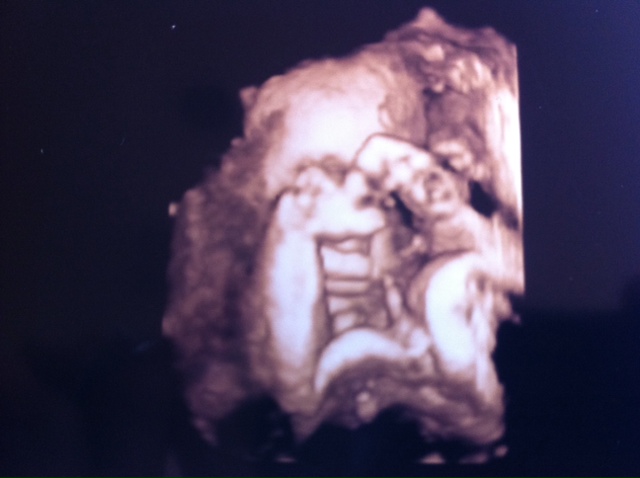

Meeting the little guy

Unfortunately, he wasn't being overwhelmingly cooperative when we went to get our 3d ultrasound - he pretty much stayed balled up te whole time, so there was either a foot, a hand, or an umbilical cord blocking his little face. This ended up being the best of all the shots we ended up with. The tech said she would try again on my next regularly scheduled ultrasound, so I may have some more in the future.

All the same, how amazing to get to see him for the first time, and put a face to all those little nudges and kicks (and some not so little!) I can't get over how chubby his little cheeks are!

In his pic, his little hands are both kind of to the left, his head's kind of laying on the placenta to the left, and the umbilical cord is the glop on the right of the picture.

We're both kind of in awe - and j just can't quit looking at this picture :-)